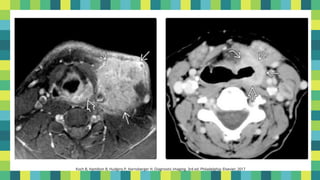

12

Koch B, Hamilton B, Hudgins P, Harnsberger H. Diagnostic imaging. 3rd ed. Philadelphia: Elsevier; 2017

13